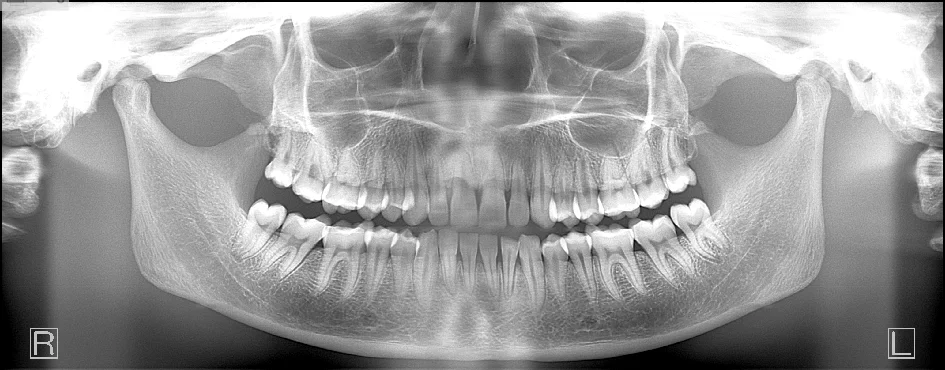

“These images are awesome”

–Dr. Mark Sheklian, Manasquan, NJ

What’s so great about a Direct Conversion Sensor?

Every scan captures over 50 different panoramic layers!

With most panoramic x-ray units, the arch of the patient needs to be exactly where the machine wants: along the path where the beam is focused.

- If positioning is not precise, a poor image can result.

- If the patient shifts slightly during the time the operator walks out to initiate the scan, a poor image can result.

- If the patient’s arch doesn’t match the trajectory of the scan, certain anatomy may not be in focus.

- The emergence profile of the anteriors could make it difficult to capture both mandibular and maxillary apices clearly in the panoramic scan.

The Panoura 18S also has Multi-Focal Plane capture capability. This means that every scan captures many layers both forward and backward. This creates a wide “envelope” where much more data is captured around where the patient is positioned.

Great images even if your staff’s technique is less than perfect!

“I just purchased the Panoura 18S from ImageWorks and absolutely love it. The image quality is fantastic, and the image can actually be improved post capture with their software (Focal trough can be altered). I highly recommend it.” –Dr. Craig Smith, Dallas, TX

“I am constantly complimented by other dentists on the quality of our radiographs.” — Dr. Scott Nawy, Timonium, MD